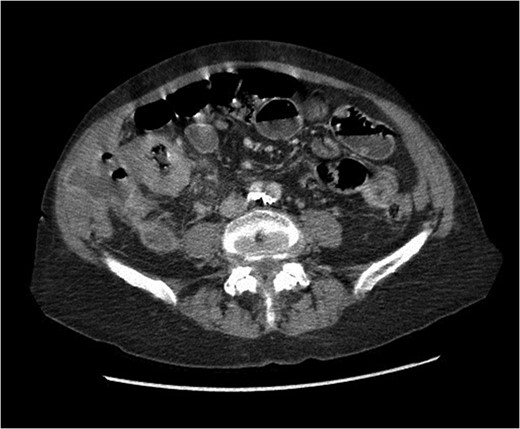

At presentation her vital signs were stable. Abdominal exam revealed exquisite tenderness in the right lower quadrant, with no evidence of digital clubbing. Blood-work revealed an elevated WBC of 15.6. A CT scan demonstrated a 4.3 cm annular mass within the cecum, suspicious for a primary colonic malignancy, as well as an 8.6 × 8.2 cm2 lobulated gas-containing abscess with extension in to the lateral abdominal wall (Figs 4 and 5).

Abdominal CT scan showing annular cecal mass with evidence of perforation.

Coronal view of abdominal CT scan showing cecal mass with evidence of perforation.